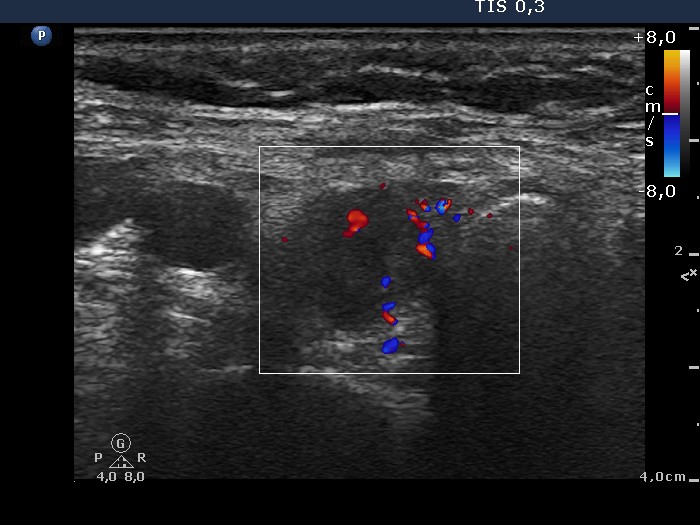

First examination (first and second rows of images):

Clinical data: A 62-year-old woman was operated on Graves' disease 15 years ago. She did not require replacement therapy. She was now referred for an evaluation of palpation and 7 kg weight loss and recurrent nodule described on ultrasonography.

Ultrasonography. A diffusely hypoechogenic thyroid was found with small more hypoechogenic areas. The hypoechogenic area was surrounded with echonormal tissue. This pattern was interpreted falsely as a nodule by a previous examiner. The vascularization was average.

Comment. It is worth analyzing the ultrasound presentation - a large hypoechogenic area is surrounded with a thick echonormal rim. Although this pattern seems to be a nodule, it is one of the most characteristic appearances of a subtotally resected thyroid.